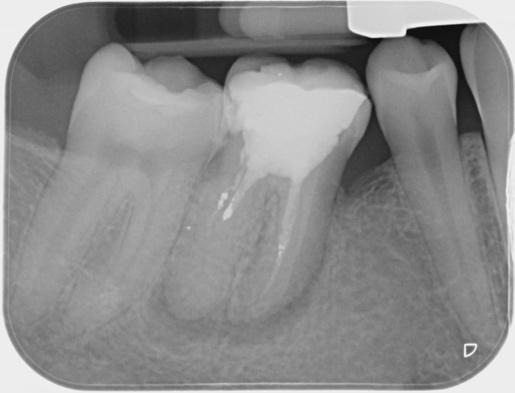

IOPA Pre-Op

The initial diagnosis here was of a failed root treatment and a symptomatic apical periodontitis. After further investigation a few extra obstacles reared their heads. The most obvious one was the blockage in the distal canal that turned out to be amalgam. In addition to this there was a ledge in the mb canal. Due to the large PARL visible on the pre-op IOPA, achieving patency in this case seemed pivotal to its success. The distal canal was unblocked using Satelec’s Endo Success kit. After that it became quite straight forward to manage and was completed over 2 visits utilising calcium hydroxide as an inter-visit medicament. The ledge in the mb canal was bypassed via the ml canal as these canals were confluent utilising the same portal of exit. Re-root treatment was initiated with Dentsply’s Reciproc silver R25 due to the rigidity of the root filling, and then completed using Wave One Gold small as the canals became quite narrow and curved apically. Copious irrigation and activation with the Ultra X was followed by obturation using WVC and AH+. It was then back to the RD for cuspal coverage.